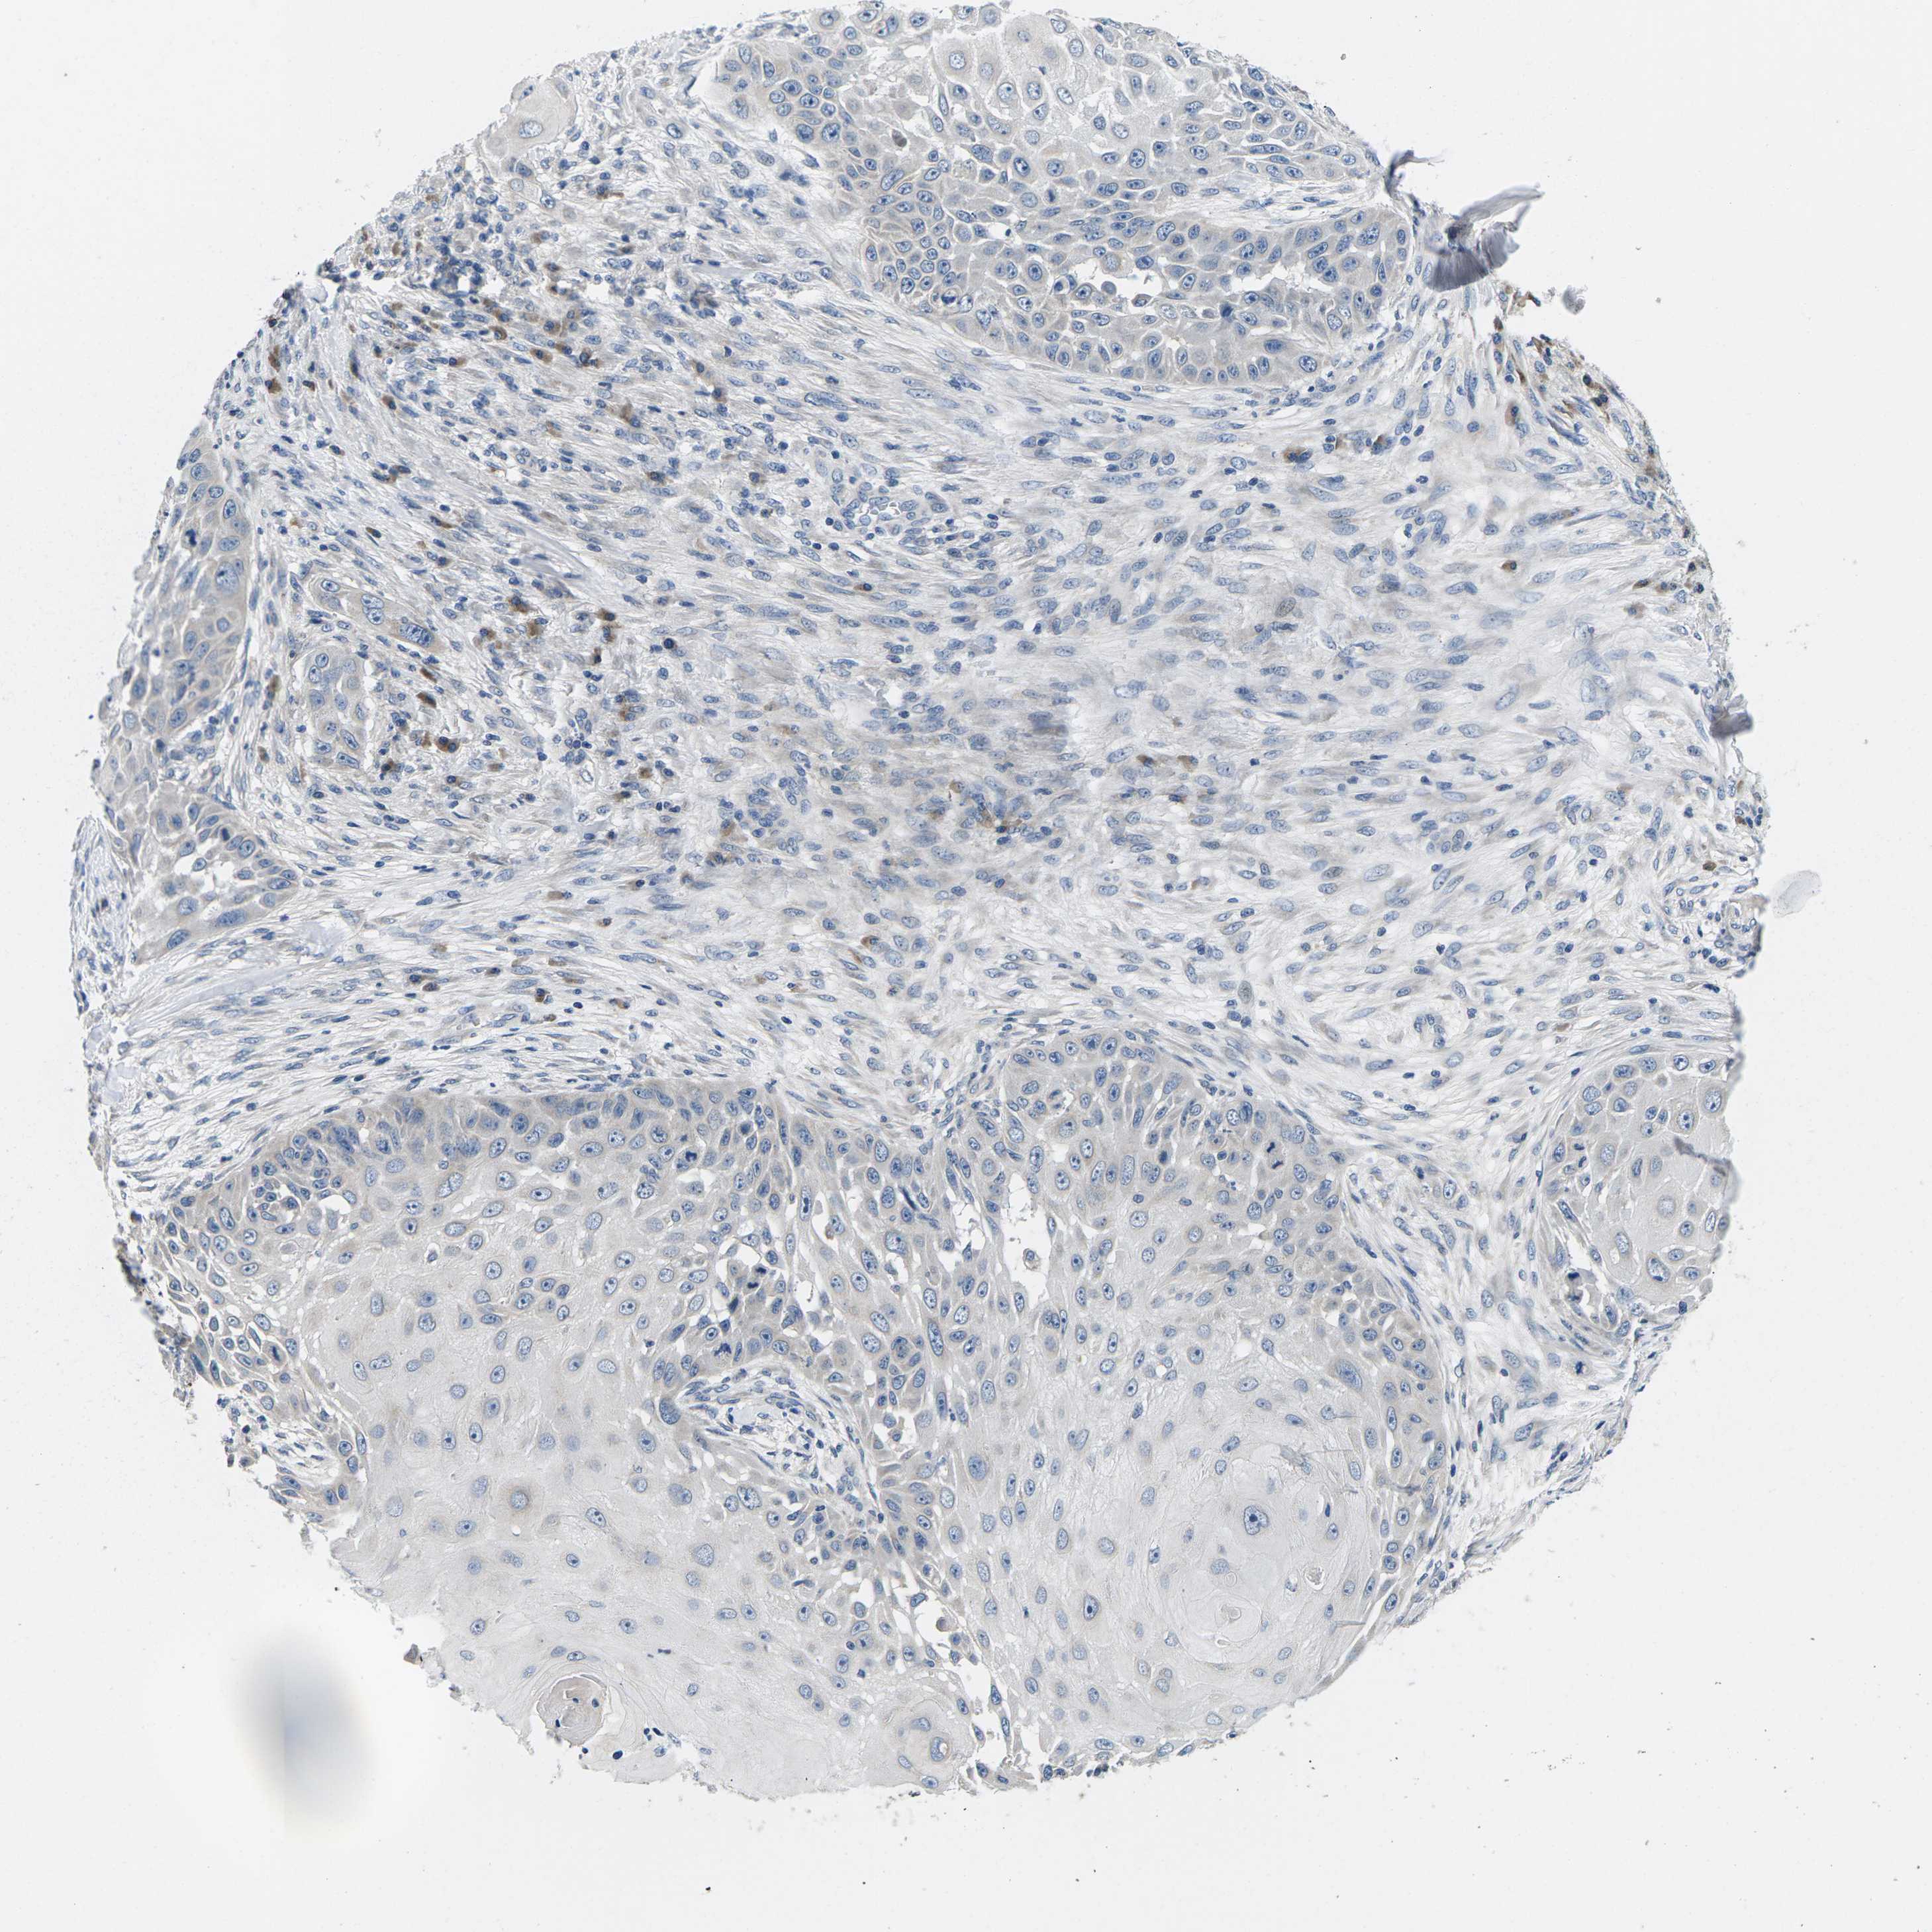

SKIN CANCER - Protein expressioni

A mouse-over function shows sample information and annotation data. Click on an image to view it in a full screen mode. Samples can be filtered based on level of antibody staining by selecting one or several of the following categories: high, medium, low and not detected. The assay and annotation is described here.

Antibody staining in the annotated cell types in the current human tissue is reported as not detected, low, medium, or high, based on conventional immunohistochemistry profiling in selected tissues. This score is based on the combination of the staining intensity and fraction of stained cells.

Each image is clickable and will lead to virtual microscopy that enables deeper exploration of all samples and also displays staining intensity scores, fraction scores and subcellular localization as well as patient and tissue information for each sample.

Antibody HPA015242

Antibody HPA015968

Squamous cell carcinoma, metastatic, NOS

Basal cell carcinoma

Squamous cell carcinoma in situ, NOS

Squamous cell carcinoma, NOS